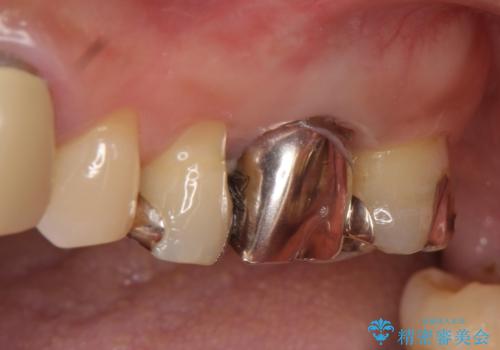

外れそうで不適合のかぶせ物の根管治療からの再治療